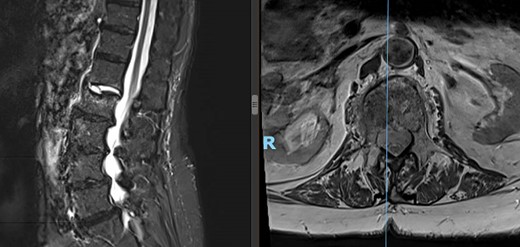

Patient’s lateral (left) and axial (right) MRI following the kyphoplasty procedure, demonstrating L1 fracture with retropulsion and compression of the conus.

Two-week postoperative check revealed the patient was still feeling disabled, with a new onset of burning pain in the right groin and thigh, severe back soreness, numbness, and leg weakness, which were refractory to pain medications. Lumbosacral spine MRI redemonstrated the cemented L2 compression fracture with posterior bony retropulsion, along with progressive collapse of the anterior inferior corner of L1 impacted into the anterior aspect of the cemented L2 compression fracture, associated kyphosis at L2, and multilevel degenerative disk changes (Fig. 3). After an extensive review of possible management options for the patient’s symptoms, the patient elected to undergo an open-approach multilevel PPSF.